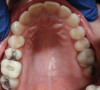

Fig 2. Occlusal view highlighting the erosive wear present on the lingual aspects of the maxillary anterior teeth with a preserved enamel ring around the gingival margin.

Figure 2

Gastric reflux, whether voluntary or involuntary, can be very destructive to tooth structure. During an intraoral examination, several factors can suggest to the clinician an active or past presence of GERD. Much like most extrinsic cases of erosion (from GERD or bulimia), the wear presents as smooth lingual surfaces of the maxillary anterior teeth and flattened occlusal surfaces of mandibular posterior molars.8 This erosive wear evolves over time and destroys the enamel except along the gingival margin, giving the teeth a darker hue.9 As the lingual surfaces of the maxillary teeth begin to erode, the teeth often respond by undergoing dentoalveolar extrusion.10 This process needs to be identified and diagnosed appropriately when proceeding with a smile design change to achieve an ideal cosmetic result. In this patient's case, dentoalveolar extrusion of the maxillary anterior teeth was diagnosed as a secondary condition resulting from the long-standing reflux condition.